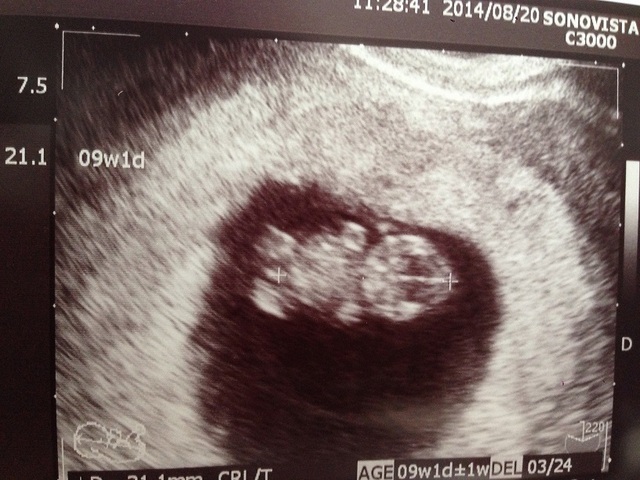

8週1日(8w1d・女の子)| あさみ0601 さん(29歳)

エコー写真撮影時のエピソード:

初めて行ったときは8週なのに心音がきこえず、とても心配でした。翌週の9週ではちゃんときけたので一安心でした。

妊娠がわかったときはとてもうれしくて、思わずにやけるほどでした。主人や両親も喜んでくれましたし、そこから安定期に入り、無事出産できて本当に良かったです。